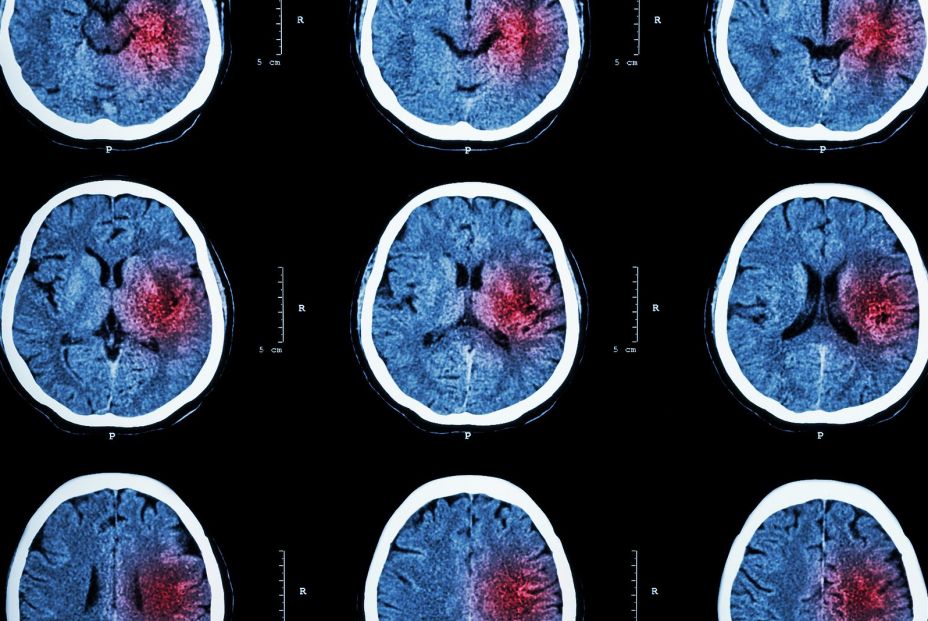

El momento del día en que se produce el ictus condiciona su gravedad y la recuperación del paciente, según un estudio liderado por investigadores del Centro Nacional de Investigaciones Cardiovasculares (CNIC), que revela hallazgos sobre la regulación que ejerce el reloj biológico interno en los neutrófilos, células inmunes que pueden agravar la lesión isquémica infiltrándose en el cerebro.

El ictus isquémico es una de las principales causas de muerte y discapacidad en el mundo. A pesar de los avances en el tratamiento agudo, la evolución de los pacientes sigue siendo muy variable, lo que indica la existencia de mecanismos biológicos aún poco comprendidos. Este trabajo, publicado en Circulation Research, identifica la regulación circadiana de la respuesta inmune como uno de ellos.

Para llegar a estas conclusiones, el equipo investigador ha trabajado con modelos experimentales de ratón y datos clínicos de más de 500 pacientes. Así, ha encontrado que, en determinadas fases del día, los neutrófilos adoptan un perfil más proinflamatorio y liberan con mayor intensidad trampas extracelulares de neutrófilos (NETs), unas estructuras que pueden obstruir la microcirculación cerebral, causar inmunotrombosis y agravar la lesión.

De este modo, cuando los neutrófilos liberan más NETs, la circulación en los pequeños vasos se ve comprometida y el daño cerebral es mayor, según ha detallado la investigadora del CNIC Sandra Vázquez-Reyes, actualmente en el Hospital General de Massachusetts, afiliado a la Facultad de Medicina de Harvard (Estados Unidos).